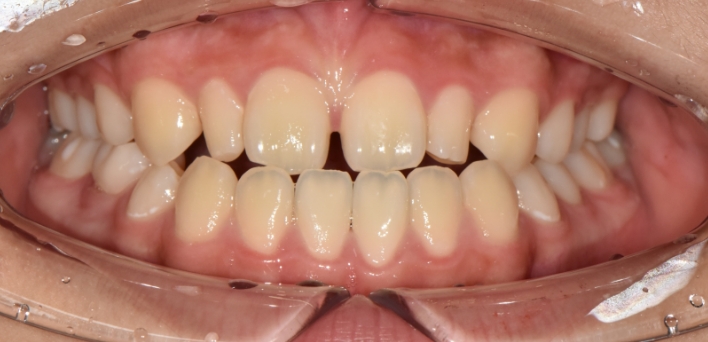

더서울을 만나, 이제 치아도 숨을 쉽니다.

치아 삭제량을 줄여 치아보존으로 진행하는 숨쉬는 라미네이트

Aesthetic treatment that preserves natural teeth

우리 얼굴에서 미소는 첫인상을 좌우합니다. 이런 좋은 인상을 위해 라미네이트를 고려 중이시라면,

많은 것들을 고려해야 합니다. 라미네이트 시 무조건 하얗고, 얇기만 한 치아가 좋은 것은 아닙니다.

개개인의 얼굴마다 비율에 맞게 이상적인 치아의 형태가 있습니다.

더서울치과의원은 정확한 안모 분석을 통한 프로파일 예측 치료로 심미성은 물론 치아 본연의 기능 회복까지 가능하도록

안면 근육과 기능, 치아 형태, 비율, 크기, 교합, 색감 등 전반적인 비율을 맞추어 본인에게 잘 맞는 치아의 형태로 복원합니다.